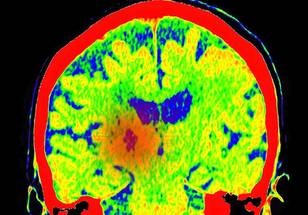

SEPTEMBER 9, 2024, NEW YORK – A Ludwig Cancer Research study has discovered that recurrent tumors of the aggressive brain cancer glioblastoma multiforme (GBM) grow out of the fibrous scars of malignant predecessors destroyed by interventions such as radiotherapy, surgery and immunotherapy.

Led by Ludwig Lausanne’s Johanna Joyce, Spencer Watson and alumnus Anoek Zomer and published in the current issue of Cancer Cell—where it is featured on the cover—the study describes how these scars enable the regrowth of tumors and identifies drug targets to sabotage their malignant support. It also demonstrates the efficacy of such combination therapies in preclinical trials using mouse models of GBM.